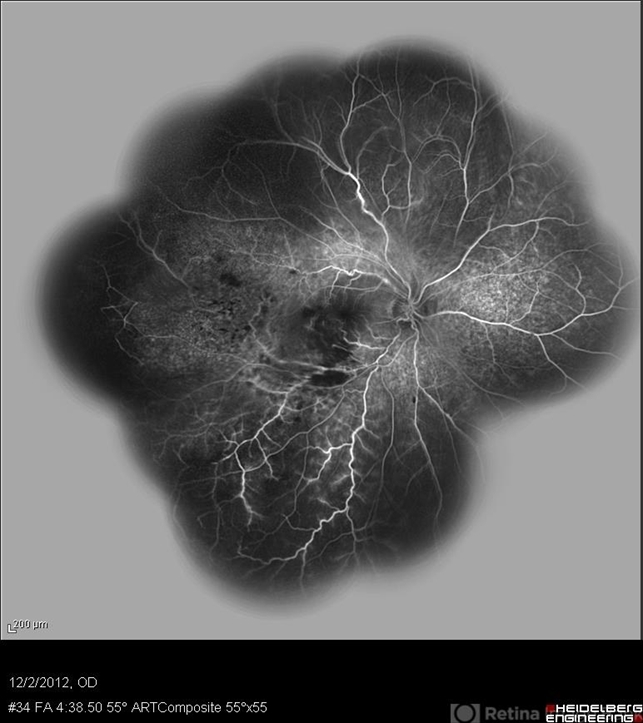

- retinal vasculitis, branch retinal vein occlusion (BRVO)

- Solmaz Shahmohammad, Negah Eye Center, Tehran

- Heidelberg Spectralis

- Wide field FA of the right eye of a 23-year-old man with retinal vasculitis and branch retinal vein occlusion (BRVO) due to Behcet's disease .